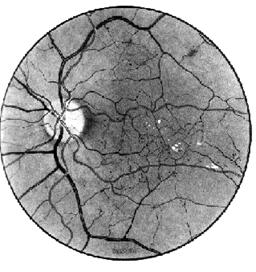

Fig. 17.2 - Angioscleroza retiniana hipertensiva

- modificarile retiniene sunt reprezentate de:

aparitia de hemoragii superficiale striate sau mai rar profunde punctate;

aparitia de noduli vatosi, sub aspectul unor mici pete albicioase cu margini sterse, cu contur neregulat cu aspect alb-cenusiu, ce reprezinta zone de microinfarctizare retiniana;

edem retinian prin cresterea reflexului retinian;

exsudate dure reprezentand expresia organizarii edemului retinian, sub forma de pete alb-galbui, stralucitoare, bine delimitate, in general determinate de lipidele extravazate prin peretele vascular; la nivelul regiunii maculare sunt dispuse intre fibrele nervului optic, dand aspectul de stea maculara (Fig. 17.3).